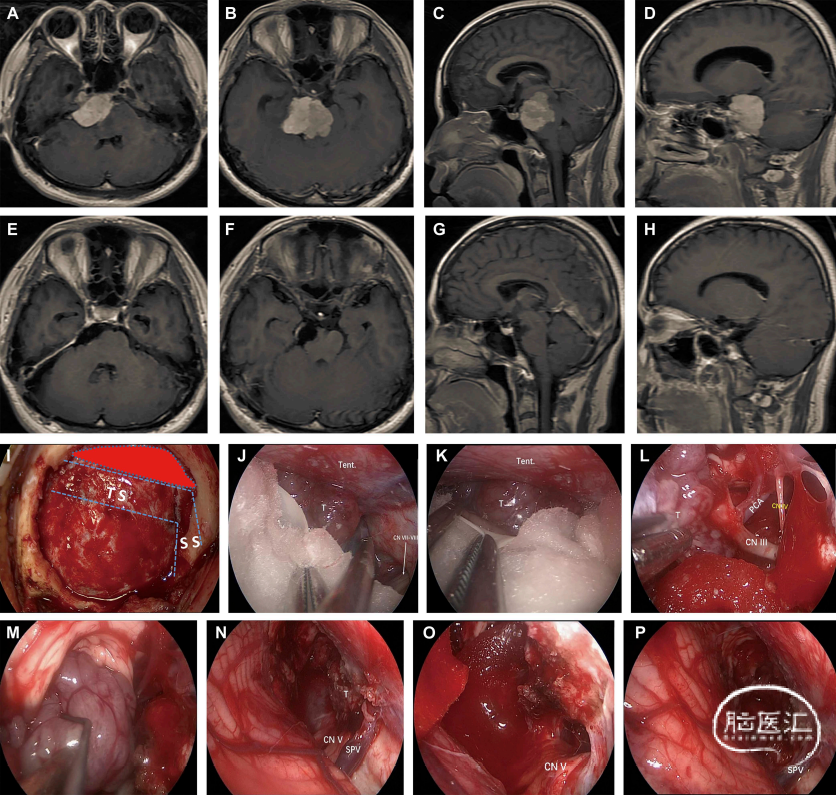

图2:图A-D显示右侧岩斜区脑膜瘤患者术前轴位及矢状位增强MRI影像(肿瘤累及岩尖、斜坡、CPA区、Meckel囊区),脑干明显受压变形;图E-H示肿瘤全切除后11月轴位及矢状位增强MRI影像;图I显示骨窗大小、横窦上方和乙状窦内侧缘的暴露(TS:横窦,SS:乙状窦);图J显示沿天幕下小脑上空间暴露分离肿瘤的外上方(Tent:天幕,CN VII-VIII:面听神经);图K显示分离肿瘤内上方(T:肿瘤);图L显示分离肿瘤与动眼神经(CN III:动眼神经,CN IV:滑车神经,PCA:大脑后动脉);图M显示分离肿瘤与脑干;图N显示大部分肿瘤切除后术野(CN V:三叉神经,SPV:岩上静脉);图O:显示从Meckel囊内三叉神经上方刮除肿瘤后术野(CN V:三叉神经);图P:显示肿瘤切除后,岩上静脉保留。